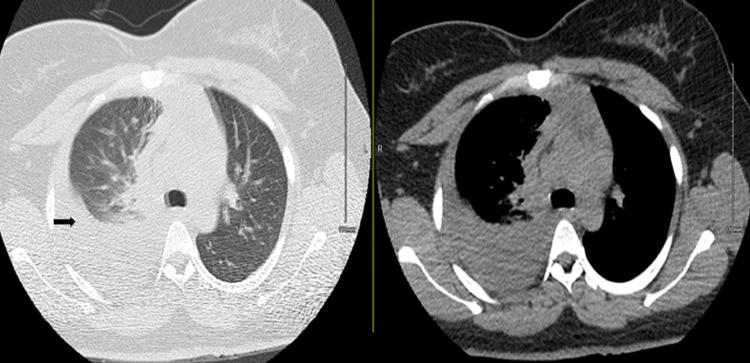

Community-acquired pneumonia is a leading cause of death from infectious diseases globally. Parapneumonic effusion is one of the most common complications of community-acquired pneumonia. As the infection progresses within the pleural space, loculation and empyema may develop. In rare cases, the parapneumonic effusions can progress significantly within 24 hours, which has been described as explosive pleuritis and may confer additional morbidity. Group A is the leading causative microorganism, which in itself has higher rates of parapneumonic effusions. We describe the case of a 30-year-old-female with a past medical history of asthma who presented to the emergency department with a sore throat, cough, and runny nose and was discharged on the same day after treatment of asthma exacerbation with upper respiratory tract infection. She re-presented within 24 hours with shortness of breath and right-sided pleuritic chest pain. Chest x-ray showed a new, large right-sided pleural effusion for which pleural fluid culture grew group A . She ultimately had prolonged hospitalization, requiring chest tube placement, and video-assisted thoracoscopic surgery (VATS). VATS was unsuccessful and she was treated with long-term antibiotics. This case demonstrates the dramatic evolution of explosive pleuritis and highlights the typical challenges encountered in these cases.

社区获得性肺炎是全球感染性疾病导致死亡的主要原因之一。类肺炎性胸腔积液是社区获得性肺炎最常见的并发症之一。随着感染在胸腔内进展,可出现分隔和脓胸。在罕见情况下,类肺炎性胸腔积液可在24小时内显著进展,这被描述为暴发性胸膜炎,可能会带来额外的发病率。A组是主要的致病微生物,其本身导致类肺炎性胸腔积液的发生率较高。我们描述了一名30岁女性的病例,她有哮喘病史,因咽痛、咳嗽和流涕到急诊科就诊,在治疗哮喘急性加重合并上呼吸道感染后于当天出院。她在24小时内再次就诊,出现气短和右侧胸膜炎性胸痛。胸部X线显示右侧有新的大量胸腔积液,胸腔积液培养生长出A组 。她最终住院时间延长,需要放置胸管,并接受了电视辅助胸腔镜手术(VATS)。VATS手术未成功,她接受了长期抗生素治疗。该病例展示了暴发性胸膜炎的急剧演变,并突出了这些病例中遇到的典型挑战。